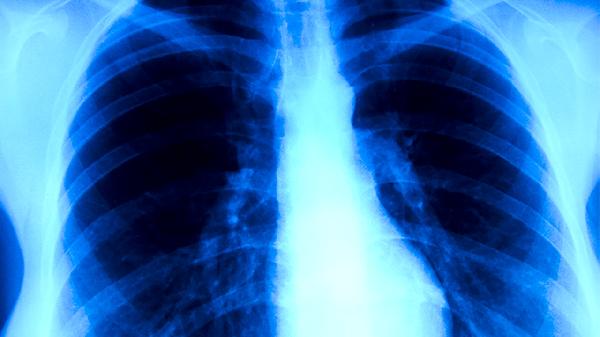

肺积水胸腔积液多数情况下无需手术,可通过胸腔穿刺引流、药物治疗、病因治疗等方式缓解。是否手术主要取决于积液量、病因及对保守治疗的反应,常见影响因素有感染性积液、恶性肿瘤、心力衰竭、低蛋白血症、结核性胸膜炎等。